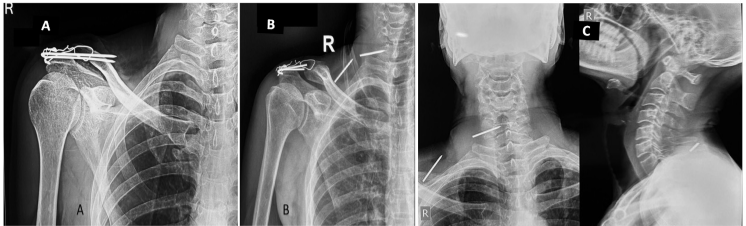

A middle-aged male in his fifties presented to our institution with a 3-year history of persistent right-sided neck and shoulder pain. The pain, localized to the posterior neck and right supraclavicular region, had been managed symptomatically at multiple local healthcare facilities without definitive relief. There was no radiation of pain or paraesthesia in either upper limb. The patient had previously been treated for cervical spondylosis, with partial symptom relief following analgesics; however, the symptoms persisted. On detailed history, the patient reported having undergone surgical fixation for a right shoulder fracture 6 years prior (Fig. 1a).

Figure 1: Old radiograph of the right shoulder showing tension band wiring of the acromioclavicular joint and a malunited but healed lateral end clavicle fracture (a); Recent radiograph of the right shoulder (b) and neck demonstrating two broken K-wire fragments migrated to the posterior neck on the right side-one located in the right supraclavicular region and the other at the posterior aspect of the neck (c).

Clinical examination revealed no signs of radiculopathy, motor weakness, or restriction in neck mobility. However, a palpable small swelling (3 × 2 cm) was noted in the right supraclavicular region. The carotid artery was well palpated, and the swelling was lateral to the vascular bundle. Radiographs of the shoulder and neck revealed two broken K-wire fragments – one located in the right supraclavicular region and another posteriorly near the cervical spine (Fig. 1b and c). The shoulder radiograph showed a malunited lateral end clavicle fracture fixed with tension band wiring over two K-wires, both of which were broken distally. A non-contrast computed tomography (CT) scan of the neck was performed to delineate the exact position of the migrated wires (Fig. 2). The case was reviewed in a multidisciplinary team setting with input from an otorhinolaryngology expert. Routine pre-operative laboratory investigations were within normal limits, and the patient was planned for elective hardware removal.